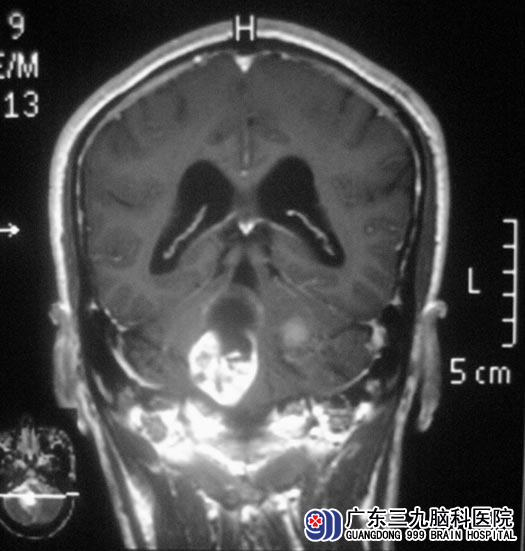

在广东三九脑科医院综合神经外科住院后,进一步MR检查发现:“双侧桥小脑角区多发占位性病变,左侧听神经增粗、强化,大小约30.6mm×29.1mm×33.7mm;右侧听神经未见强化,大小约为32.7mm×26.9mm×47.6mm,肿瘤向下生长入颈静脉孔”;考虑多发神经鞘膜瘤。